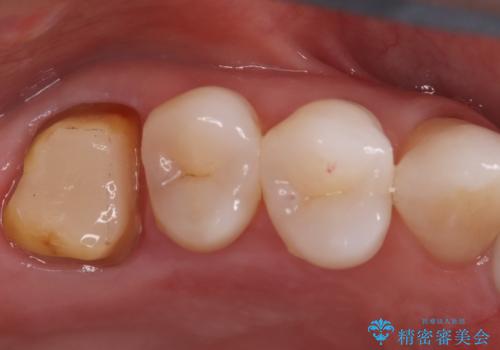

- 「奥歯の詰め物が取れた」という主訴でご来院されました。レントゲンおよび視診の結果、詰め物が外れた内部で虫歯が再発しており、根の先にも炎症が見られたため、再根管治療(根の再治療)が必要と診断しました。 特に上顎の大きな奥歯(第一大臼歯)は、通常の根管以外に「MB2」と呼ばれる隠れた根管が存在することが多く、これが未処置のままだと再発の原因となります。そこで、歯科用顕微鏡(マイクロスコープ)を用いて徹底的に内部を清掃し、その後、強度と審美性に優れたオールセラミッククラウンで修復する計画を立案しました。

顕微鏡によるMB2の発見: 歯科用顕微鏡(マイクロスコープ)を使用し、根管内を強拡大して観察したところ、事前の予想通り、従来の治療では見逃されていた**第4の根管「MB2」**を発見しました。この未処置だった根管内の汚れを徹底的に除去・消毒することで、痛みの再発リスクを根本から取り除きました。

オールセラミッククラウンによる修復: 根管内が清潔に封鎖されたことを確認した後、土台を立てて歯の形を整えました。最終的な被せ物には、金属を一切使用しないオールセラミッククラウンを選択。天然歯のような透明感を再現し、高い適合性によって再び虫歯になるリスクを抑えています。